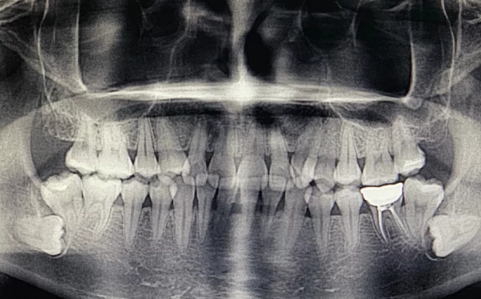

牙医建议拔掉智齿主要是因为牙齿反复发炎,会影响邻近的牙齿。

1、反复炎症:智齿出牙不完整,龈冠覆盖后侧部分形成冠周袋。不注意个人卫生,局部软组织往往会发炎,出现疼痛症状,所以需要拔掉智齿才能有效改善。

2、影响邻近牙齿:如果牙齿生长位置不正确而拥挤,就有可能对邻近牙齿造成损害,使咀嚼功能严重受损,因此需要拔除智齿。

在拔智齿时需要选择正规医院,有经验的医生来操作。此外,还需要在医生指导下服用消炎药,防止感染。